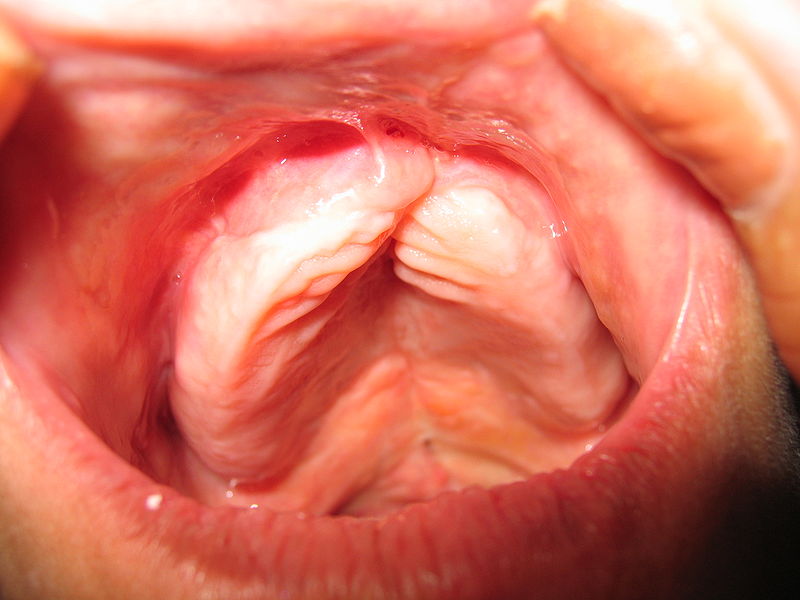

Oral Candidiasis

Candida is a yeast organism that is often present in minute amounts in regular saliva, is a frequent cause of oral thrush infection.

Candida is harmless to healthy individuals.

Candida overgrowth can happen in people whose immune systems have been compromised by disease or drugs.

As a result, the tissues in the mouth become inflamed, and “thrush” (a whitish crust or coating on the tongue’s surface) develops.

Risk factors for oral candidiasis (“thrush”) include:

- Antibiotic use like penicillin or cephalosporin

- Cancer chemotherapy drugs like cyclophosphamide

- Steroids

- Radiation therapy

- HIV/AIDS medications

- Organ transplant recipients

- Diabetes

- Weakened immune systems

- Severe burn injuries

- Leukemia

Thrush can occasionally progress into the potentially dangerous disorder oropharyngeal candidiasis (OPC).